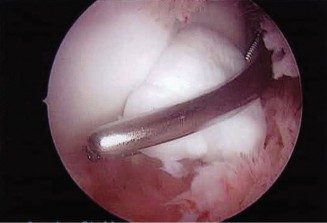

Figure 3: Arthroscopic view during debridement and preparation of a capitellar OCD lesion prior to marrow stimulation. Note the debrided cartilage and the exposed subchondral bone.

1. Arthroscopic Debridement and Marrow Stimulation (Microfracture)

- Indications: Stable but symptomatic lesions with cartilage fissuring or softening (fibrillation), or unstable fragments that are too small or comminuted for fixation, typically less than 2-3 cm² in size, with healthy surrounding cartilage.

Technique:

- Thorough debridement of all unstable or delaminated cartilage from the lesion bed, creating stable vertical shoulders.

- Using a motorized shaver or curette, the sclerotic subchondral bone is meticulously removed until bleeding bone is exposed.

- A microfracture awl or a K-wire through a cannula is then used to create multiple small perforations (microfractures) in the subchondral bone, spaced 3-4 mm apart, to a depth of 2-4 mm. This encourages egress of mesenchymal stem cells from the bone marrow, promoting fibrocartilage formation.

- Loose bodies, if present, are removed using graspers.